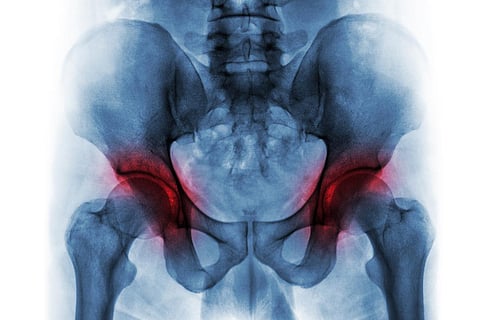

A hip replacement is performed when someone has severely damaged cartilage in a hip joint. The hip joint is a ball-and-socket joint located in the groin area, and when it’s damaged, it may cause groin pain, buttock pain and/or pain on the side of the hip. Pain from a damaged hip joint may also radiate down the thigh and cause referred pain to the knee joint on the same leg.